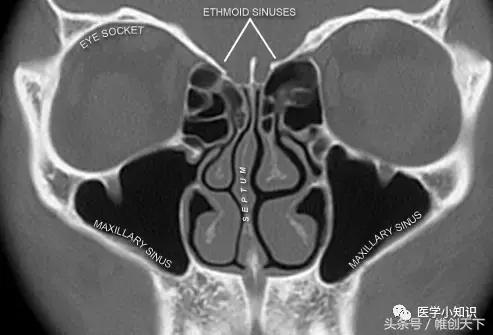

鼻窦是脸部骨骼中充满气体的空腔,这些空腔内充满着黏膜。人类的鼻窦可分为四群:

上颚窦位于两脸颊里侧

额窦在两眉毛后上方

筛窦沿着鼻根中线两侧往深部沿伸

蝶窦紧邻筛窦后面

鼻窦炎是指一个或多个鼻窦发生炎症。鼻纤膜(如图所示)有将鼻窦细菌和粘液清除的功能,当鼻子内粘膜发炎、肿胀鼻窦内的液体无法排出,就会出现鼻窦疼痛等情况。感染和过敏都会使鼻窦出现发炎、红肿引起鼻窦疾病。